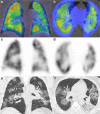

Medical imaging methods are assuming a greater role in the workup of patients with COVID-19, mainly in relation to the primary manifestation of pulmonary disease and the tissue distribution of the angiotensin-converting-enzyme 2 (ACE 2) receptor. However, the field is so new that no consensus view has emerged guiding clinical decisions to employ imaging procedures such as radiography, computer tomography (CT), positron emission tomography (PET), and magnetic resonance imaging, and in what measure the risk of exposure of staff to possible infection could be justified by the knowledge gained. The insensitivity of current RT-PCR methods for positive diagnosis is part of the rationale for resorting to imaging procedures. While CT is more sensitive than genetic testing in hospitalized patients, positive findings of ground glass opacities depend on the disease stage. There is sparse reporting on PET/CT with [18F]-FDG in COVID-19, but available results are congruent with the earlier literature on viral pneumonias. There is a high incidence of cerebral findings in COVID-19, and likewise evidence of gastrointestinal involvement. Artificial intelligence, notably machine learning is emerging as an effective method for diagnostic image analysis, with performance in the discriminative diagnosis of diagnosis of COVID-19 pneumonia comparable to that of human practitioners.